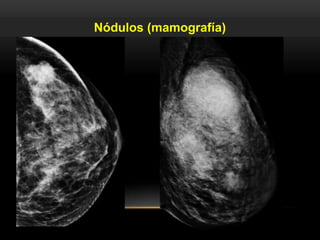

Lesión ocupante de espacio visible en dos proyecciones.

Nódulos (mamografía)